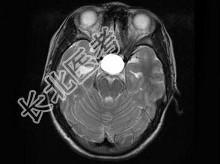

- 单项选择题男,19岁, 视力模糊1周,MRI检查如图所示应诊断为 ( )

A、颅咽管瘤

B、脑膜瘤

C、垂体瘤卒中

D、脑膜膨出

E、未见异常